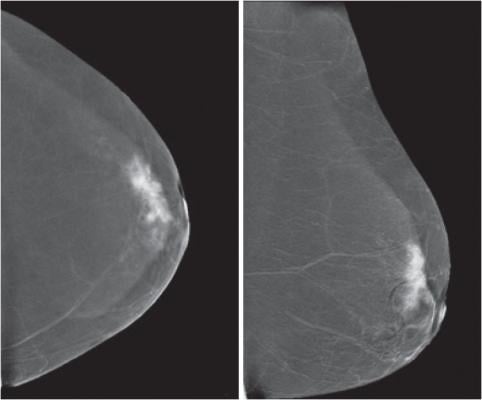

"While increased use of screening mammography has significantly contributed to improved detection of breast cancer, substantial disparities in breast cancer screening exist among populations in the country," said the study's lead author, Soudabeh Fazeli Dehkordy, M.D., M.P.H., from St. John Providence Hospital in Southfield, Michigan. "We sought to determine whether increasing access to health insurance through Medicaid expansion has resulted in improved breast cancer screening adherence."

Using data from the 2008 and 2012 Behavioral Risk Factor Surveillance System and adjusting for age, education, income and race, the analysis showed that low-income women in expansion states had a similar likelihood of being screened to those in non-expansion states in 2008. However, in 2012, after the early expander states implemented their programs, low-income women in expansion states were 25 percent more likely to be screened for breast cancer than in 2008.